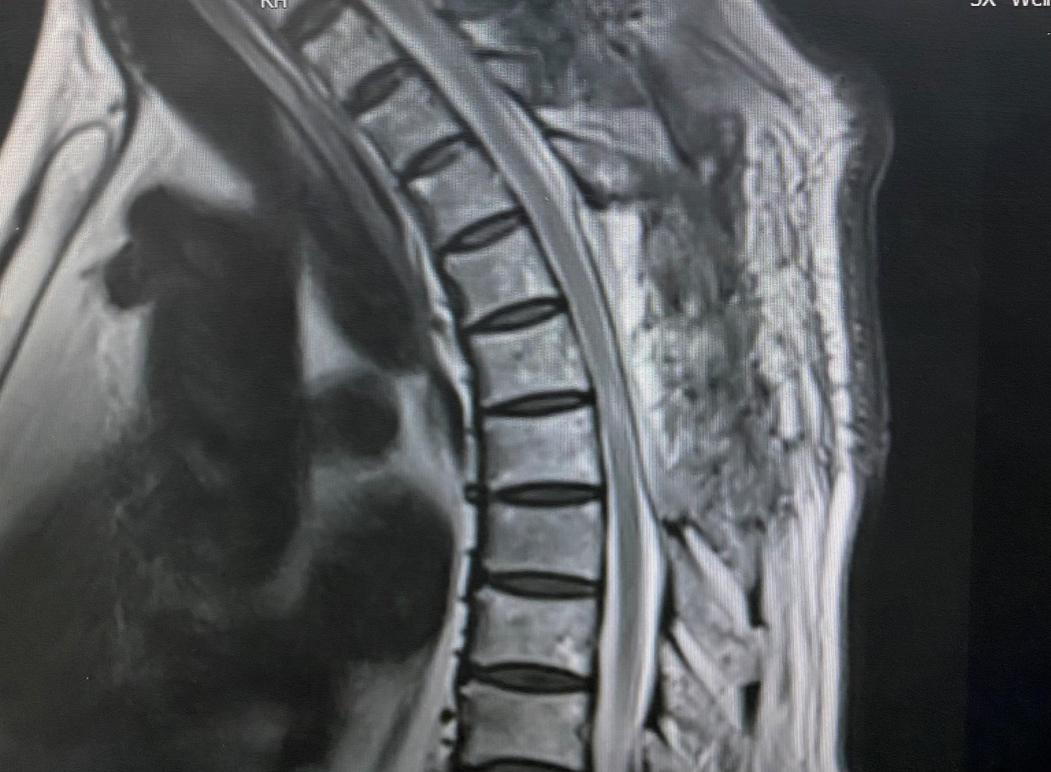

患者男性,66岁,1年前患者无明显诱因出现双下肢无力、麻木等症状,活动稍受限,多方治疗效果不佳。1月前,感足趾僵硬,并逐渐向上延伸至膝关节,同时伴小便失禁,查体见患者步态不稳、行走缓慢,步距小,踝关节及足趾跖屈力量减弱,脐以下感觉明显减退。入院后行胸椎MRI检查提示胸4-7椎体水平椎管内占位性病变,结合影像学资料综合考虑血管脂肪瘤。

由于患者的肿瘤位于胸4-7椎体水平,术前检查提示肿瘤血供丰富,肿瘤体积大,脊髓明显受压变薄,且下肢已出现不全瘫,括约肌功能受损,任何小的牵拉、刺激都可能损伤脊髓致肌力进一步下降,甚至截瘫,严重影响患者生存质量。加上此类疾病十分罕见,因此患者入院后科室高度重视。